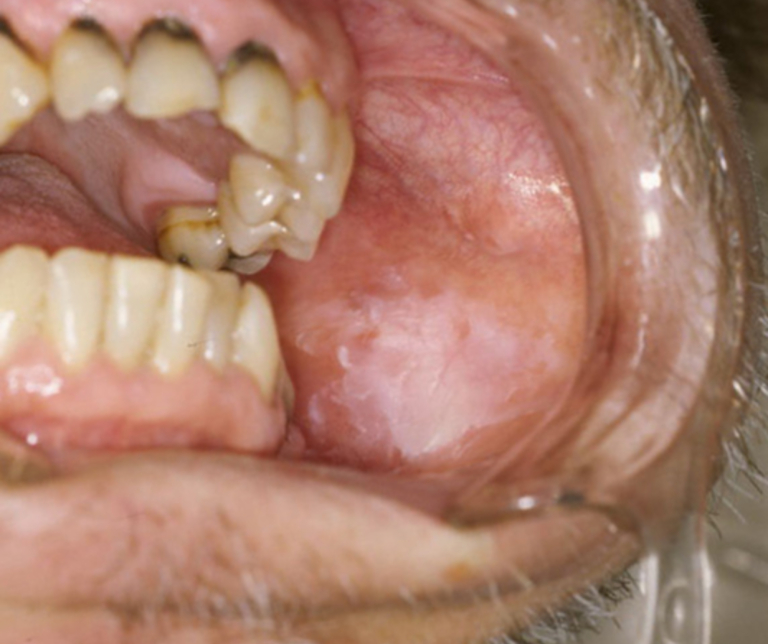

治らない口内炎・色の変化(口腔粘膜疾患)

もっとも注意深く拝見するのが、単なる口内炎と見分けがつきにくい異変です。

白板症(はくばんしょう)や紅板症といった「がん化する可能性のある状態(前がん病変)」や、初期の口腔がんの可能性があります。

痛みがないことも多く、特に「2週間以上、形や色が変わらずに残っている」場合は要注意です。

白斑(はくはん)

歯茎や頬の裏に、こすっても取れない「白い板」のような模様がある。

紅斑(こうはん)

粘膜の一部がテカテカと赤くなっている。

当院の対応

表面の状態、境界線を詳細に観察します。

少しでも疑わしい場合は、即座に専門病院での組織検査を手配します。